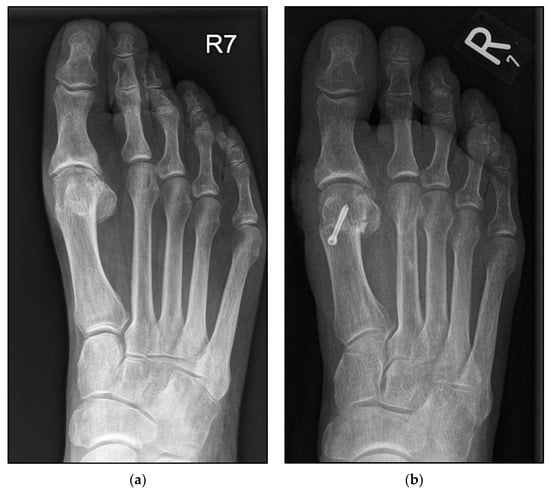

The Conventional Weil Osteotomy Does Not Require Screw Fixation

2.3. Surgical Procedure Using the Second Metatarsal as an Example